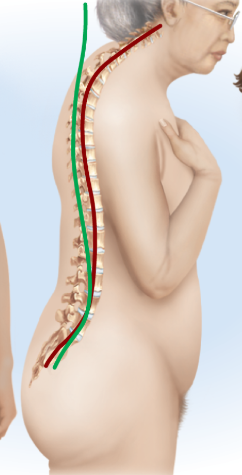

Cervical curvature

Lordosis, convex anteriorly, curves forward

Thoracic curvature

Kyphosis, concave anteriorly, curves outward

Lumbar curvature

Lordosis, convex anteriorly, curves forward

Pelvic curvature

Kyphosis, concave anteriorly, curves outward

Scoliosis

Lateral (S shape, side-to-side), thoracic region

Kyphosis

Exaggeration of thoracic curvature, overly rounded (shrimp posture)

Lordosis

Exaggeration of lumbar curvature, too far forward